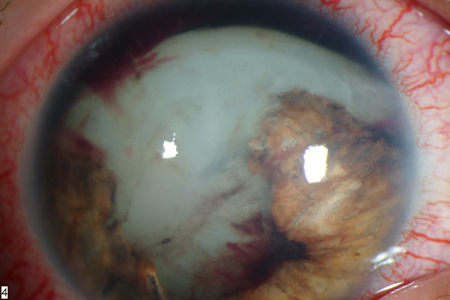

eye trauma

Cataracts may be associated with blunt or penetrating injury to the globe.[Figure caption and citation for the preceding image starts]: Traumatic cataract and iris traumaFrom the personal collection of M. Bowes Hamill, MD [Citation ends].